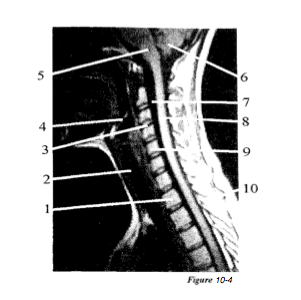

Question 4

Question

Label with the letter: A. Intervertebral disk, B. Cerebellum, C. Trachea, D. Vertebral body C-5, F. Medulla oblongata, G.Cervical cord, H.CSF, I . Epiglottis, J. Vertebral body T-1, K. Spinous process

Answer

• J

• C

• A

• I

• F

• B

• H

• G

• D

• K